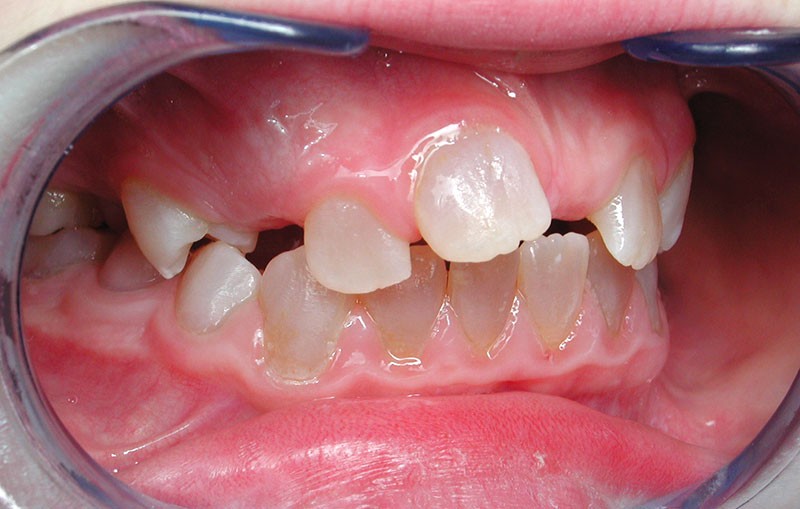

Teinte opalescente grise à jaune ambrée, couronnes globuleuses, calcifications intra-pulpaires, racines fines et courtes, attrition précoce, nécrose aseptique… Ces anomalies cliniques et radiographiques décrivent le tableau de la dentinogenèse imparfaite (DI) isolée de type 2. Cette anomalie génétique à transmission autosomique dominante est liée à un défaut de DSPP, gène de la sialophosphoprotéine dentinaire [1, 2]. Des anomalies dentinaires similaires résultent également de mutations de ce gène. Les avancées en recherche génétique tendent à réunir ces pathologies sous une même étiologie.

Un diagnostic précoce est primordial, car il existe aussi une forme associée à une anomalie osseuse, l’ostéogenèse imparfaite. Le chirurgien-dentiste est donc au premier plan pour dépister ces anomalies et limiter dès le plus jeune âge leurs conséquences infectieuses, fonctionnelles et esthétiques.